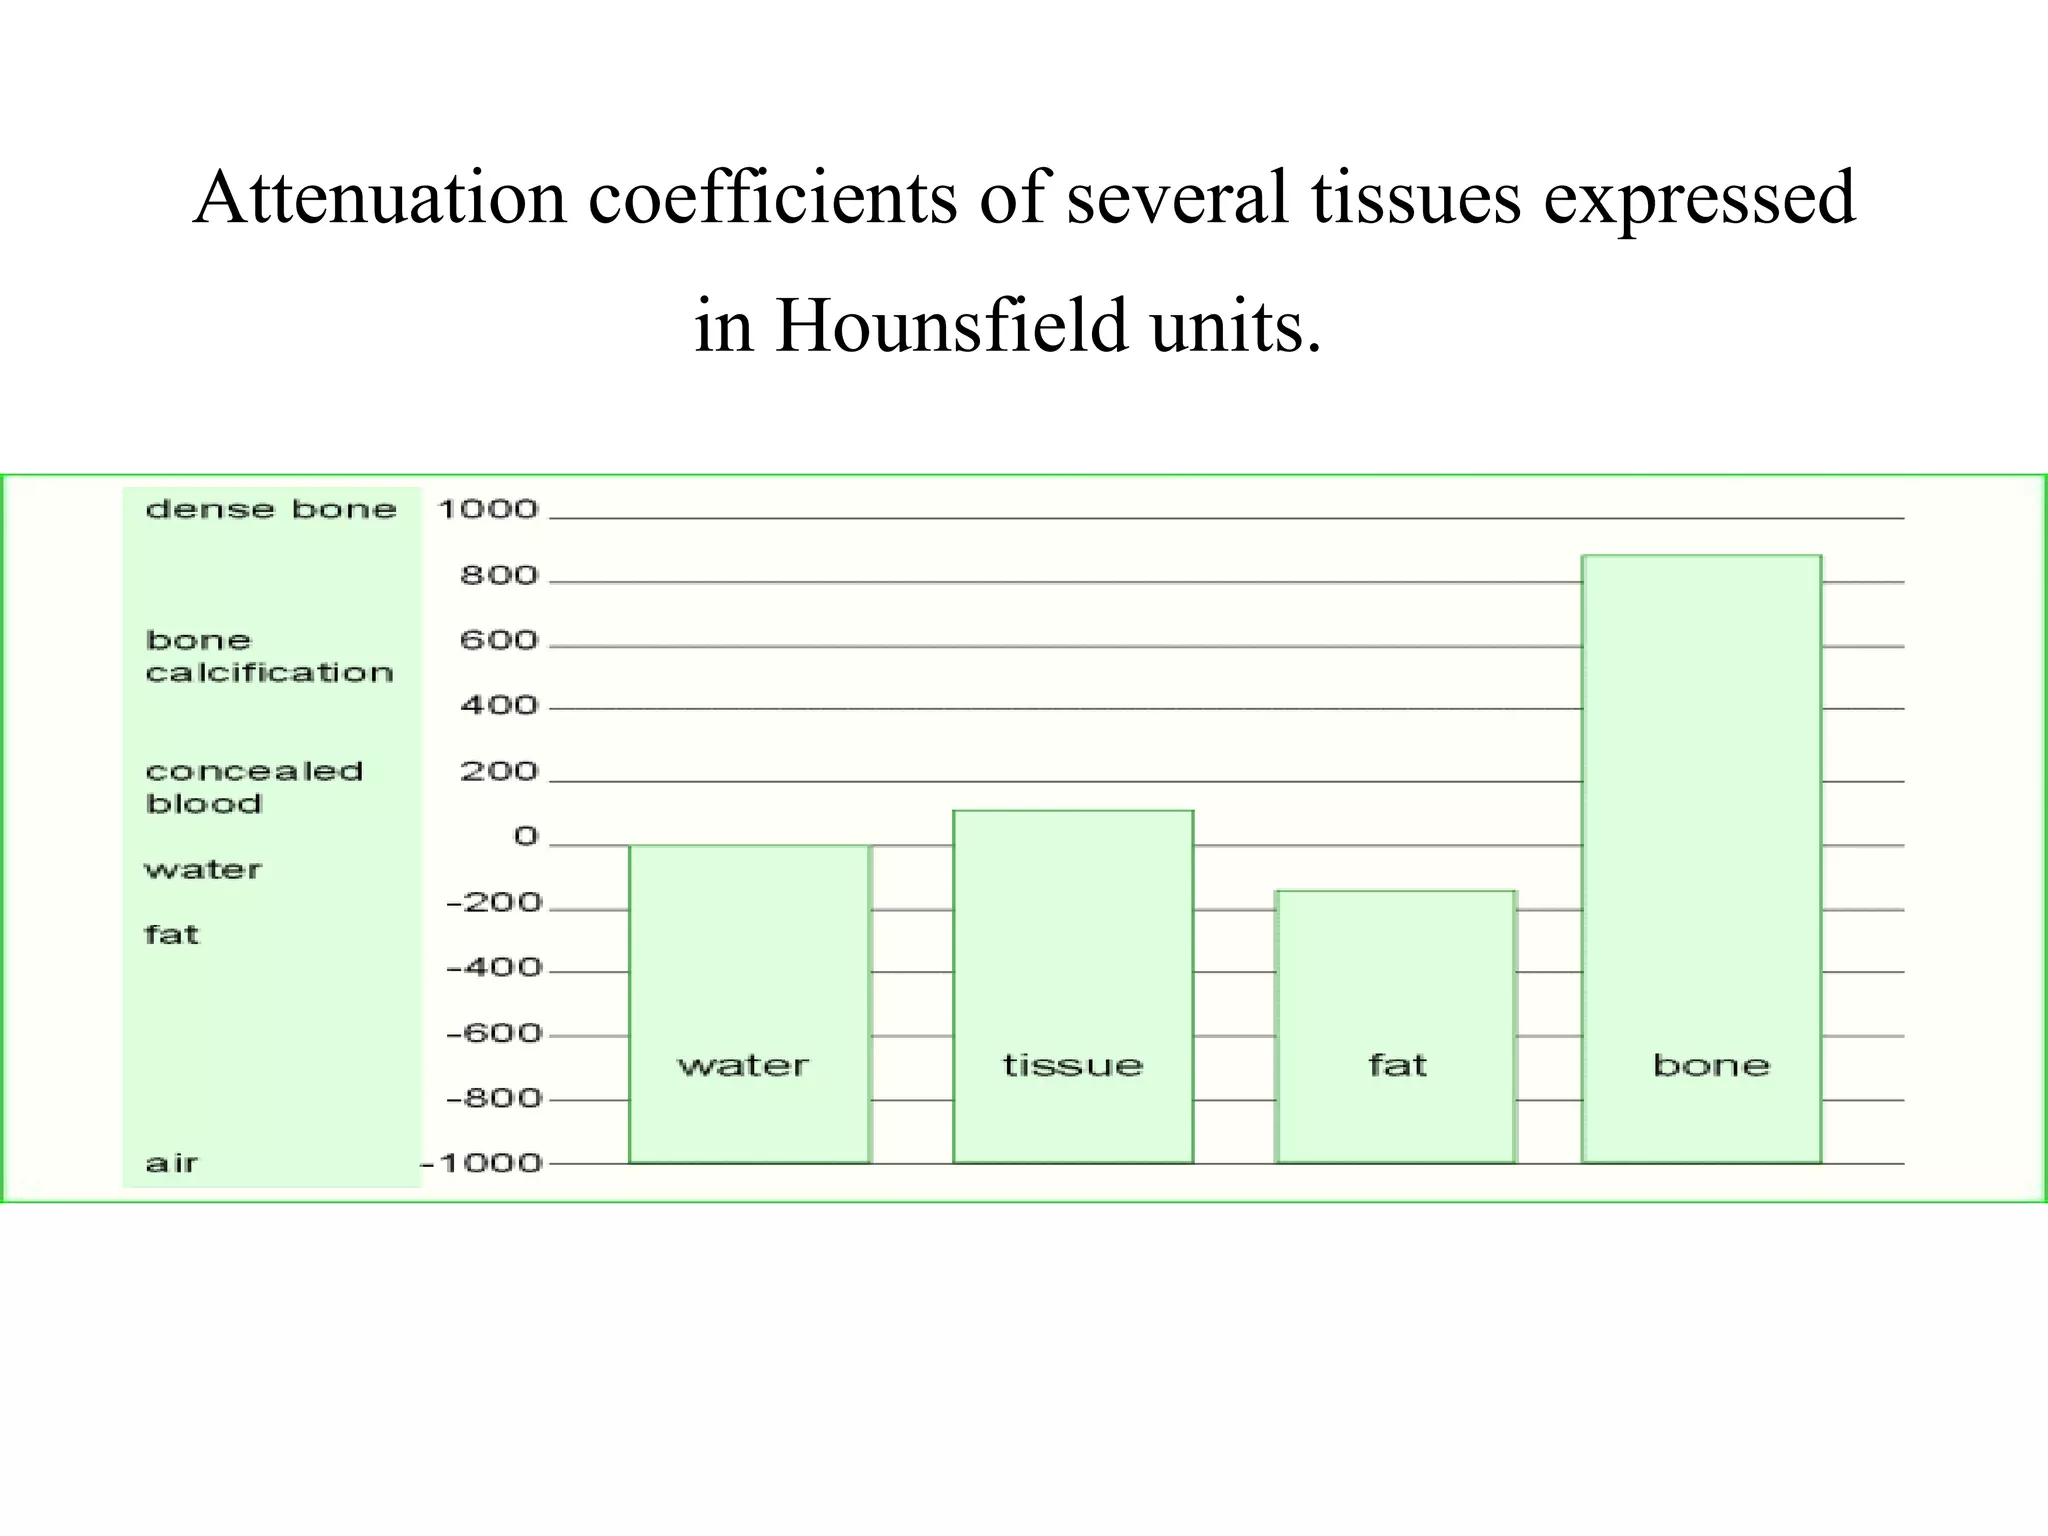

The document discusses various medical imaging modalities including x-rays, computed tomography (CT), and digital mammography. It describes the basic principles and historical development of these technologies, how images are formed, and what types of anatomical features and abnormalities they can detect. Key advances include the development of digital systems that allow image manipulation and remote consultation. While promising, digital mammography still faces challenges around resolution and cost.